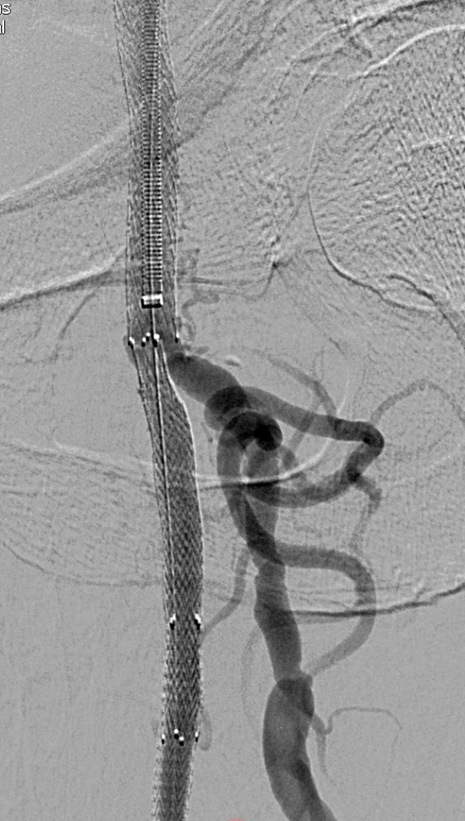

开通:以内膜下技术为主,逆穿是常用且有效的辅助手段。

预扩:充分预扩张至关重要,需逐级使用高压球囊,最终达到 6mm 直径,以获得足够的管腔。

支架植入:遵循“由远及近”原则,先放置远端 DES,再覆盖中段 VB,最后处理近端。利用 Eluvia 的可调节性优化重叠。

后扩:常规使用 6mm 高压球囊进行后扩张,确保支架充分贴壁和管腔获得。

用药:术中术后必须充分抗凝,推荐“双通道”抗栓方案(如利伐沙班+阿司匹林),以模拟 bypass 的血流动力学效果。